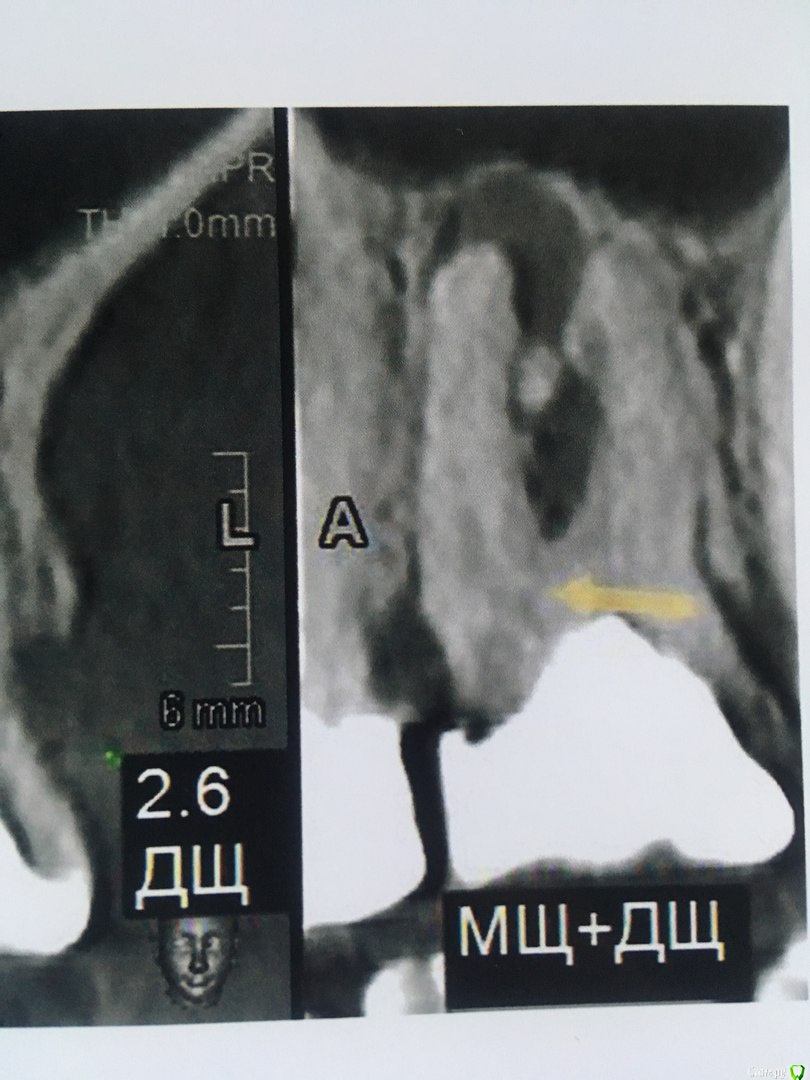

В течении  года от зуба опустилась десна и там проглядывается прозрачно-черный корень и очень быстро на 5 и 4-ки обазовались черные пятна.  Сделала КТ. Теперь стоит вопрос долгое  лечение или удаление.Врач говорит все будет видно при вскрытии. Если лечение то долгое и без гарантий.   Мне кажется от корня там мало что осталось,судя по цвету и по тому как быстро испортились рядом стоящие зубы. Может проще не лечить,установить имплант?

Правда один врач сказал,что то вроде убыли костной ткани и имплант удержать будет не чем,кроме того сужение верхней челюсти, рецессия десны и стирание в пришеечной области из за прикуса. В заключении кт -пародонтопатия легкой степени тяжести.

Добрый вечер!  Благодарю за ответ. Побывала у другого врача. Мнения разошлись. Второй доктор сказал 4,6  удаляем, а верхний 2,6 лечим.Первый же доктор сказал наоборот. Можно спросить еще Ваше мнение по 2,6 и 2,5 зубам?)